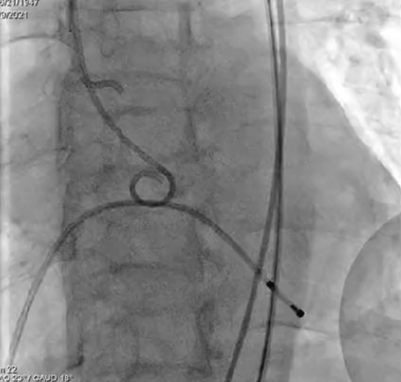

选取20mm球囊180bpm频率下快速起搏预扩。球囊扩张后未见反流,左右冠血流未受影响,选择VenusA-Plus 26型号瓣膜植入。

预扩